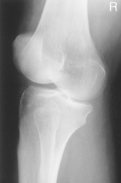

• Supine, or seated on table, with leg extended and centered to CR and midline of table or IR

• Rotate leg slightly inward as needed to place knee and leg into a true AP. Center IR to CR.

Medial oblique: Demonstrates fibular head and neck unobscured. (Lateral oblique may also be taken.)